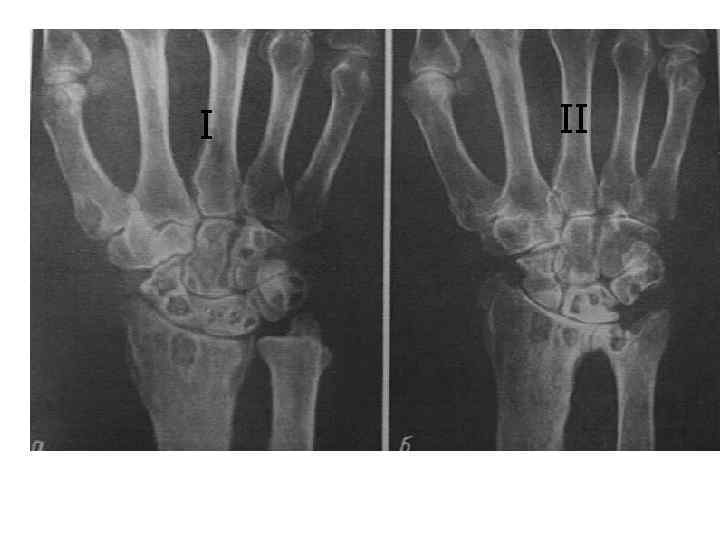

Рентгеновские снимки остеосклероза костной ткани